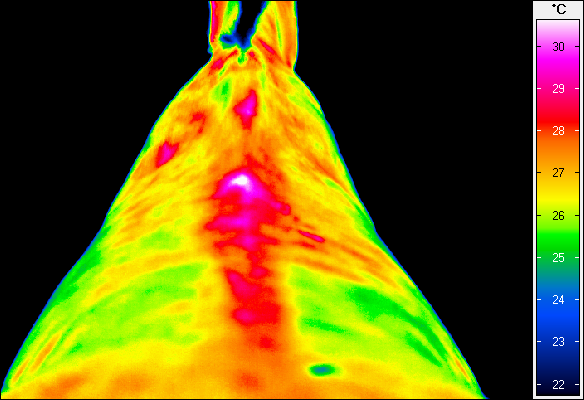

Termografia umożliwia nieinwazyjny pomiar rozkładu temperatury na powierzchni ciała konia. Wynikiem badania jest obraz – termogram, w którym poszczególne barwy odpowiadają określonym zakresom temperatur. Uzyskany rozkład cieplny odzwierciedla przede wszystkim ukrwienie tkanek powierzchownych, aktywność metaboliczną mięśni oraz właściwości izolacyjne skóry i okrywy włosowej.

W warunkach prawidłowych rozkład temperatury ciała konia charakteryzuje się wysokim stopniem symetrii pomiędzy lewą i prawą stroną. Najwyższe wartości temperatur obserwuje się w okolicach dobrze unaczynionych, takich jak oczy, nozdrza czy większe masy mięśniowe, natomiast najchłodniejsze obszary obejmują dalsze odcinki kończyn. Odstępstwa od tego wzorca – zwłaszcza asymetrie przekraczające około 1°C – mogą wskazywać na zaburzenia fizjologiczne lub rozwijające się procesy zapalne.

Metoda ta pozwala na identyfikację obszarów o podwyższonej temperaturze, związanych z zapaleniem ścięgien, więzadeł, torebek stawowych czy okostnej, często jeszcze przed pojawieniem się wyraźnych objawów klinicznych. Oprócz kończyn, istotnym obszarem zastosowania termografii jest grzbiet konia. Zaburzenia w obrębie mięśni przykręgosłupowych, więzadeł nad- i międzykolcowych czy stawu biodrowo-krzyżowego często mają charakter złożony i nie zawsze są łatwe do jednoznacznego rozpoznania przy użyciu standardowych metod. Termografia umożliwia wizualizację zmian w aktywności cieplnej tych struktur, co może wskazywać miejsca przeciążenia, bólu lub kompensacji ruchowych.